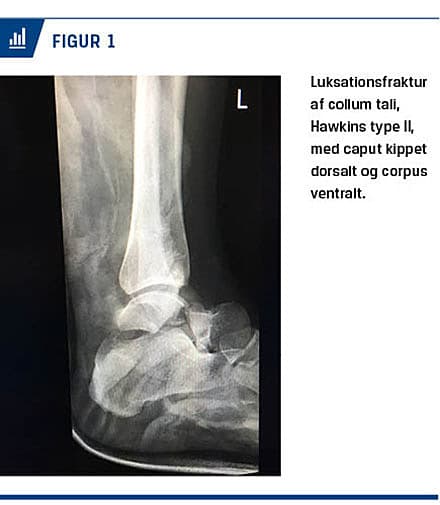

efter at hun under bygningsarbejde på et tag var faldet 3,5 m ned på jorden. Ved modtagelse på skadestuen havde hun mange smerter fra venstre fodled, som klinisk blev fundet fejlstillet med foden let inverteret og et diskret frempromenerende element anteriort. Hun var stærkt øm over malleolerne og området herimellem. Tilstanden blev af forvagten på skadestuen tolket som en disloceret bimalleolær fraktur, hvorfor der som standardpraksis blev foretaget forsøg på grovreponering og derefter gipsning af anklen. En efterfølgende røntgenoptagelse viste en luksationsfraktur af collum tali, Hawkins type II, med caput kippet dorsalt og en diastase på 12 mm centralt i frakturspalten (Figur 1). Corpus var kippet ventralt og displaceret posteriort. På en CT kunne røntgenfundet bekræftes og yderligere ossøs skade udelukkes.